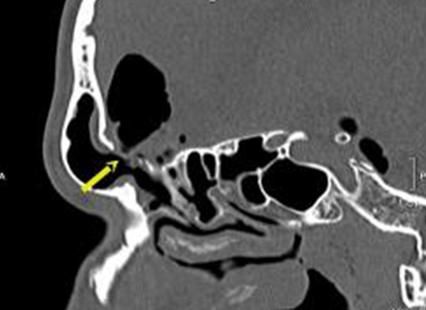

Людський організм влаштований так, що в ньому є вузькі анатомічні канали, через які проходять нервові стовбури. За нормальних умов розміри цих каналів є достатніми для функціонування нервів. Проте внаслідок деяких захворювань відбувається звуження цих каналів, що призводить до стиснення нерва і тимчасового або повного порушення його функції.

- анатомічні особливості (тунельні синдроми),

Найбільш ефективним методом лікування тунельних нейропатій є хірургічний.

У нашому відділенні виконують всі види оперативних втручань при цій патології, які проводяться через невеликі розрізи до 3 см. Через них вдається розітнути зв’язки й звільнити компресований нерв.

Всі операції проводяться під мікроскопом, з використанням мікроінструментарію, що дає нам можливість не пошкодити тонкі і ніжні нервові стовбури. Операції проводяться під місцевою анестезією і тривають до 20 хв.